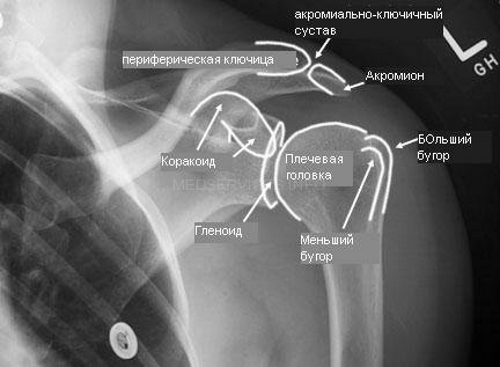

Чтобы обнаружить изменения в суставе, рентгенологу необходимо знать нормы здорового плечевого сустава. Суставная щель должна быть равномерной по всему размеру, без дополнительных образований, патологических просветлений или нарушений кортикального слоя костей, формирующих сустав.

Рентгенограмма плечевого сустава является важным инструментом в диагностике различных заболеваний и травм. Врачи отмечают, что этот метод позволяет выявить переломы, вывихи, а также дегенеративные изменения, такие как остеоартрит. На снимках можно увидеть состояние костей, суставных поверхностей и окружающих мягких тканей. Специалисты подчеркивают, что рентген помогает не только в диагностике, но и в планировании лечения. Например, при наличии перелома врач может оценить его тип и степень смещения, что влияет на выбор метода лечения — консервативного или хирургического. Однако рентгенограмма не всегда дает полное представление о состоянии мягких тканей, поэтому в некоторых случаях может потребоваться дополнительная визуализация, такая как МРТ или УЗИ.